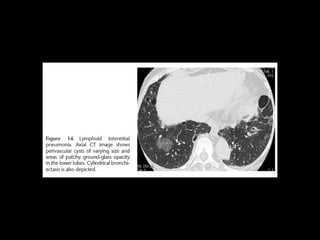

LIP

• Benigna

• Idiopática es rara

• Asociada a SS, VIH, enferemedad autoinmune

tiroides, enfermedad de castleman

M, 50

Disnea tos, fiebre artralgias,

80% disproteinemias igG igM

• Infiltración de linfocitos e histiocitos engrosando septos

LIP CT

• Vidrio esmerilado

• Nódulos

• Engrosamiento septos y peribroncovascular

• *Quistes 80% LI DD: NSIP celular

• DD: histiocitosis de langerhans,

IIP raras LIP • Benigna •Idiopática es rara • Asociada a SS, VIH, enferemedad autoinmune tiroides, enfermedad de castleman M, 50 Disnea tos, fiebre artralgias, 80% disproteinemias igG igM

• Infiltración delinfocitos e histiocitos engrosando septos

LIP CT • Vidrioesmerilado • Nódulos • Engrosamiento septos y peribroncovascular • *Quistes 80% LI DD: NSIP celular • DD: histiocitosis de langerhans, linfangioleiomiomatosis, enfisema, DIP,